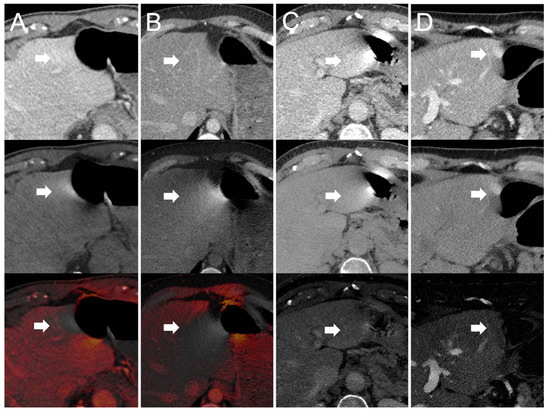

- Dual-source scanner: Depth of extension of visceral-motion-related artifacts into the liver (see Figure 2 and Figure 3) was significantly shorter (p < 0.001, each) for 120-kVp-like images (mean length: 5 ± 6 mm) compared with 40-keV (mean length: 16 ± 11 mm), 190-keV (mean length: 16 ± 9 mm), VNC (mean length: 15 ± 10 mm), and iodine (mean length: 16 ± 11 mm) images. Mean ROI measurements (HU or iodine concentration, respectively) were significantly different in the bright and dark artifact components compared to the neighboring liver parenchyma not affected by artifacts in 40-keV (p < 0.001, each), 190-keV (p < 0.001, each), VNC (p < 0.001, each), and iodine images (p < 0.001, each). However, in 120-kVp-like images, mean ROI measurements were not significantly different in bright (ROImin) artifact components compared to unaffected liver parenchyma (p = 0.32), as opposed to dark (ROImax) artifact components (p < 0.001).

- Dual-source scanner: Qualitative artifact scores (see Figure 4) were significantly lower (p < 0.001, each) for 120-kVp-like images (median score: 2, range: 1–5) compared with 40-keV (median score: 4, range: 1–5), 190-keV (median score: 3, range: 2–5), VNC (median score: 3, range: 2–5), and iodine (median score: 4, range: 1–5) images.